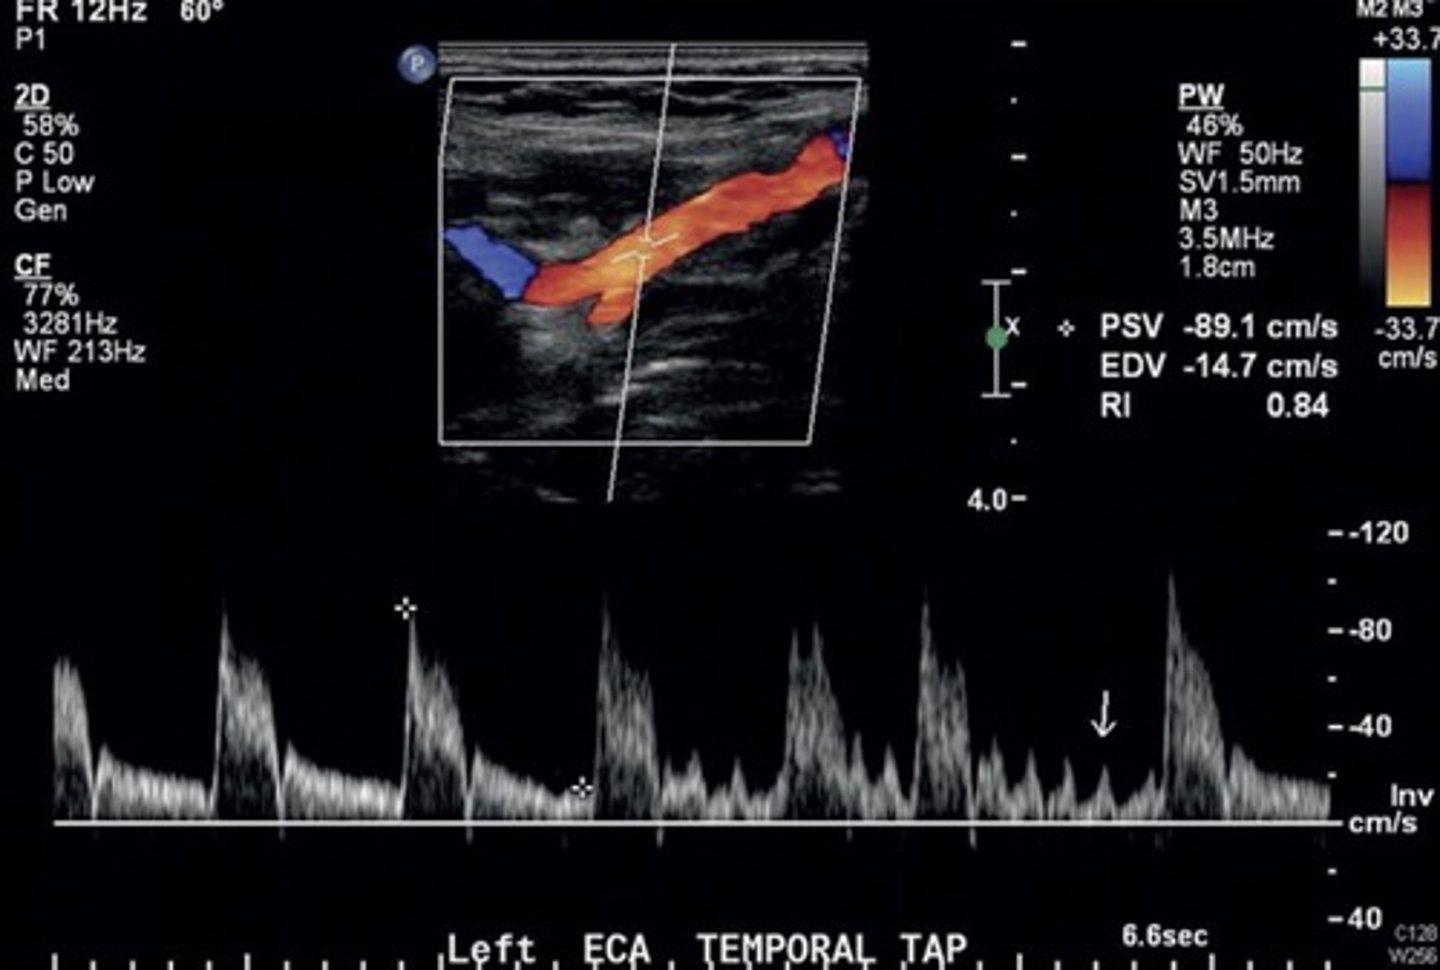

Normal ECA Waveform (with temporal tap)

High resistant